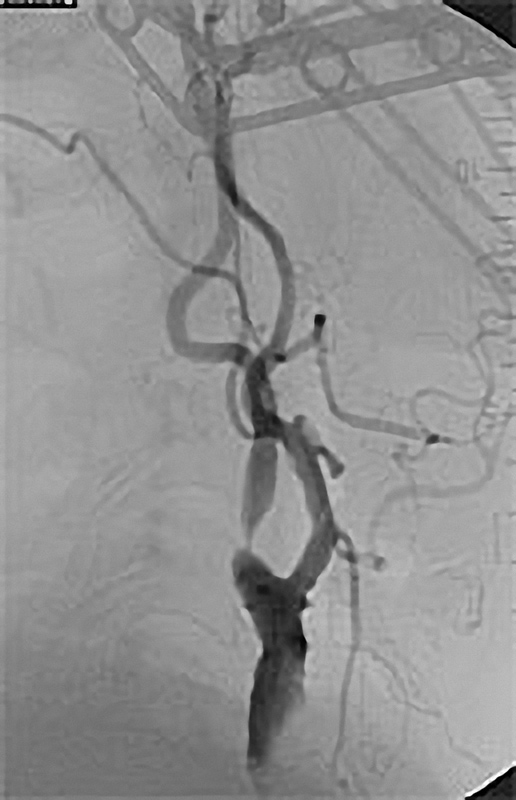

Grundprinzip der Kathetertherapie ist die Gefäßbehandlung über einen millimetergroßen Hautschnitt unter örtlicher Betäubung und das Vorschieben von Plastikschläuchen (Kathetern) in die Gefäße. Über diesen Zugang (meist in der Leisten- oder Ellenbeuge) können Gefäßeinengungen aufgeweitet oder auch Gefäßverschlüsse wiedereröffnet werden (Ballon- oder Stentverfahren). Diese Verfahren werden immer weiter entwickelt und so sind nun auch Behandlungen des Bauchaortenaneurysmatas oder das Einbringen einer Herzklappe auf diesem Wege möglich.

Möglichkeiten der Perkutanen Transluminalen Angioplastie (PTA)

Die PTA (Perkutane Transluminale Angioplastie) im Beckenbereich ist ein minimalinvasives Verfahren zur Behandlung von verengten Beckenarterien. Dabei wird ein dünner Katheter mit einem Ballon über die Leiste in die verengte Arterie eingeführt. Der Ballon wird an der Engstelle entfaltet und dehnt die Arterie auf, um den Blutfluss zu verbessern. Oft wird zusätzlich ein Stent eingesetzt, um die Arterie dauerhaft offen zu halten. Die PTA wird meist in örtlicher Betäubung durchgeführt und ermöglicht eine schnelle Erholung. Sie ist eine bewährte Alternative zur offenen Operation bei Durchblutungsstörungen im Becken- und Beinbereich.